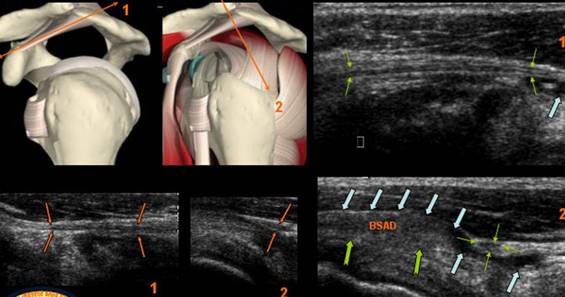

CHIST SINOVIAL GLENO HUMERAL ANTERIOR

DURERI SCAPULARE ANTERIOARE

STRUCTURA CHISTICA, TRANSSONICA,SITUATA DEASUPRA APOFIZEI CORACOIDE PRELUNGINDU-SE CU UN COLET PANA IN RECESUL SUBSCAPULAR